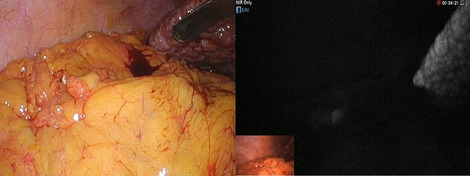

Methods: Analysis of our prospectively collected, IRB approved database of hybrid, open, and robotic esophagectomies was performed. Starting 01/2019, we implemented an updated robotic standardized anastomotic technique using a circular stapler and ICG (indocyanine green) for our RAMIE cases at our academic center (Picture 1). Outcomes of patients undergoing this standardized robotic Ivor Lewis esophagectomy for esophageal cancer from 01/2019 – 11/2020 were compared to our overall cohort from 06/2016–06/2020 (Hybrid/Open group).Propensity score matching comparing robotic to hybrid procedures will be performed and data will be presented upon the meeting.

Methods: ActivSightTM, an FDA-cleared device, consists of an imaging module (an adapter positioned between any white light camera and laparoscope) and a light engine. LSCI detects tissue perfusion without an external fluorophore and displays it to the surgeon as a color heatmap. ActivSightTM also visualizes ICG using near infrared fluorescence (NIRF). Usability was determined using human factor testing on a Likert scale (1–5) while utility was measured by comparing perfusion detection between ICG and LSCI modes (without fluorophore). Accuracy of ICG and LSCI perfusion display was determined in user post-hoc survey comparing white light, ICG, and LSCI intraoperative images from sleeve gastrectomies. Relative quantification was measured in co-axial spotlighted areas, translating a perfusion heatmap to numerical values using proprietary algorithms.

Methods: Starting 01/2019, we implemented a standardized robotic anastomotic technique using a circular stapler and ICG (indocyanine green) for our RAMIE cases at our academic center (Fig. 1). Video material of standardized RAMIE cases was recorded and criteria for selection of suitable videos for annotation were defined. Those included high video quality and performance of a standardized anastomotic phase. Anastomotic phase was defined to begin when the cautery hook touches the esophagus, and the esophagus is divided. Next a monofilament purse string suture is performed robotically. One 12-mm assistant trocar is then removed, and this incision is extended to a mini thoracotomy with a standardized length of 7 cm. The stapler head is inserted and sutured into the esophageal stump using the prepared purse string suture using the robotic instruments. Its end was defined as when the circular stapler head is successfully sutured in and the needle is cut off. Next, video annotation was performed using pixel annotation for tool identification and vector annotation for identification of instrument direction and head of the used instrument (Figs. 2 and 3).